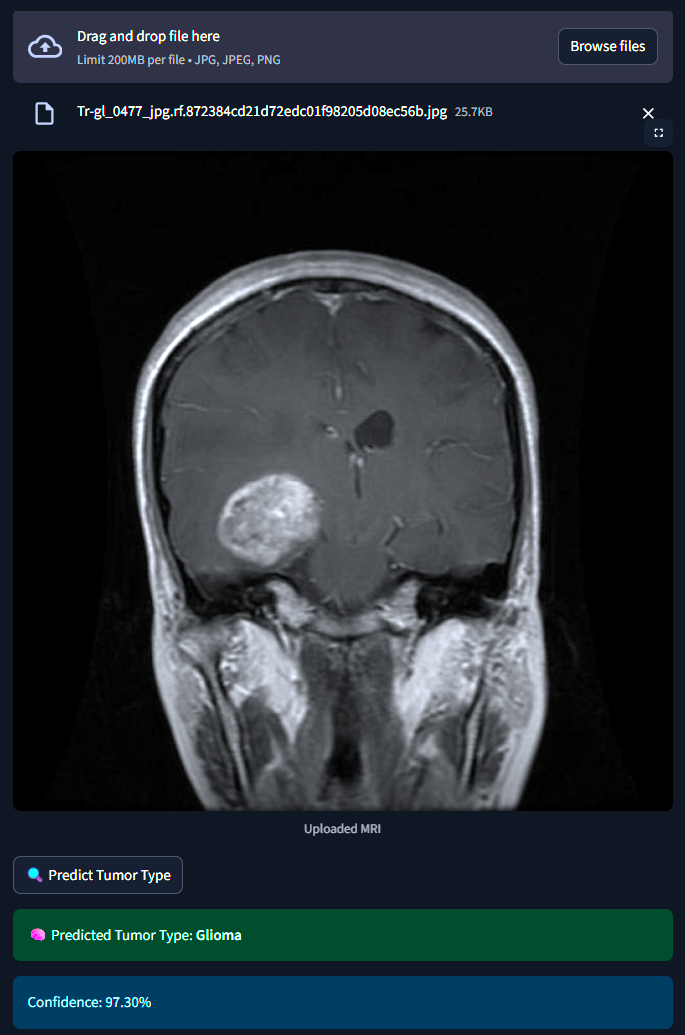

The system classifies MRI brain scans into one of four categories - Glioma, Meningioma, Pituitary Tumor or No Tumor. It uses both a Custom Convolutional Neural Network (CNN) and MobileNetV2 Transfer Learning for classification. An interactive Streamlit web app allows users to upload MRI images and receive real-time tumor predictions with probability scores.

1) Dataset :- 2,443 MRI images labeled and categorized by medical experts. 2) Preprocessing :- Used ImageDataGenerator for rescaling, rotation, zoom and flipping to augment limited data. 3) Model 1 (Custom CNN) :- Built from scratch with 3 convolutional layers, dropout and softmax classification. 4) Model 2 (MobileNetV2) :- Fine-tuned transfer learning model using pretrained ImageNet weights. 5) Training :- Used callbacks like EarlyStopping and ModelCheckpoint to optimize training and avoid overfitting. 6) Evaluation :- Tracked model performance using confusion matrix, accuracy/loss plots, and classification reports. 7) Deployment :- Developed a Streamlit web app for real-time image classification and visualization.

1) Built two deep learning models from scratch and through transfer learning. 2) Developed a clean and interactive real-time web app for medical use cases. 3) Achieved strong classification metrics despite limited and imbalanced data. 4) Successfully deployed a working prototype that can assist clinical workflows.